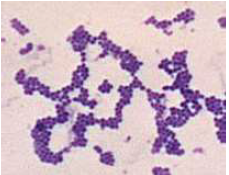

Staphylococcus (葡萄球菌,G+)

- Gram’s Positive

- Catalase 有氣泡 (區別 Streptococci)

- 兼性厭氧

- 高鹽生存

S. aureus (金黃色葡萄球菌)

- 全溶血(β hemolysis)

- Coagulase-postive (凝固酶陽性)